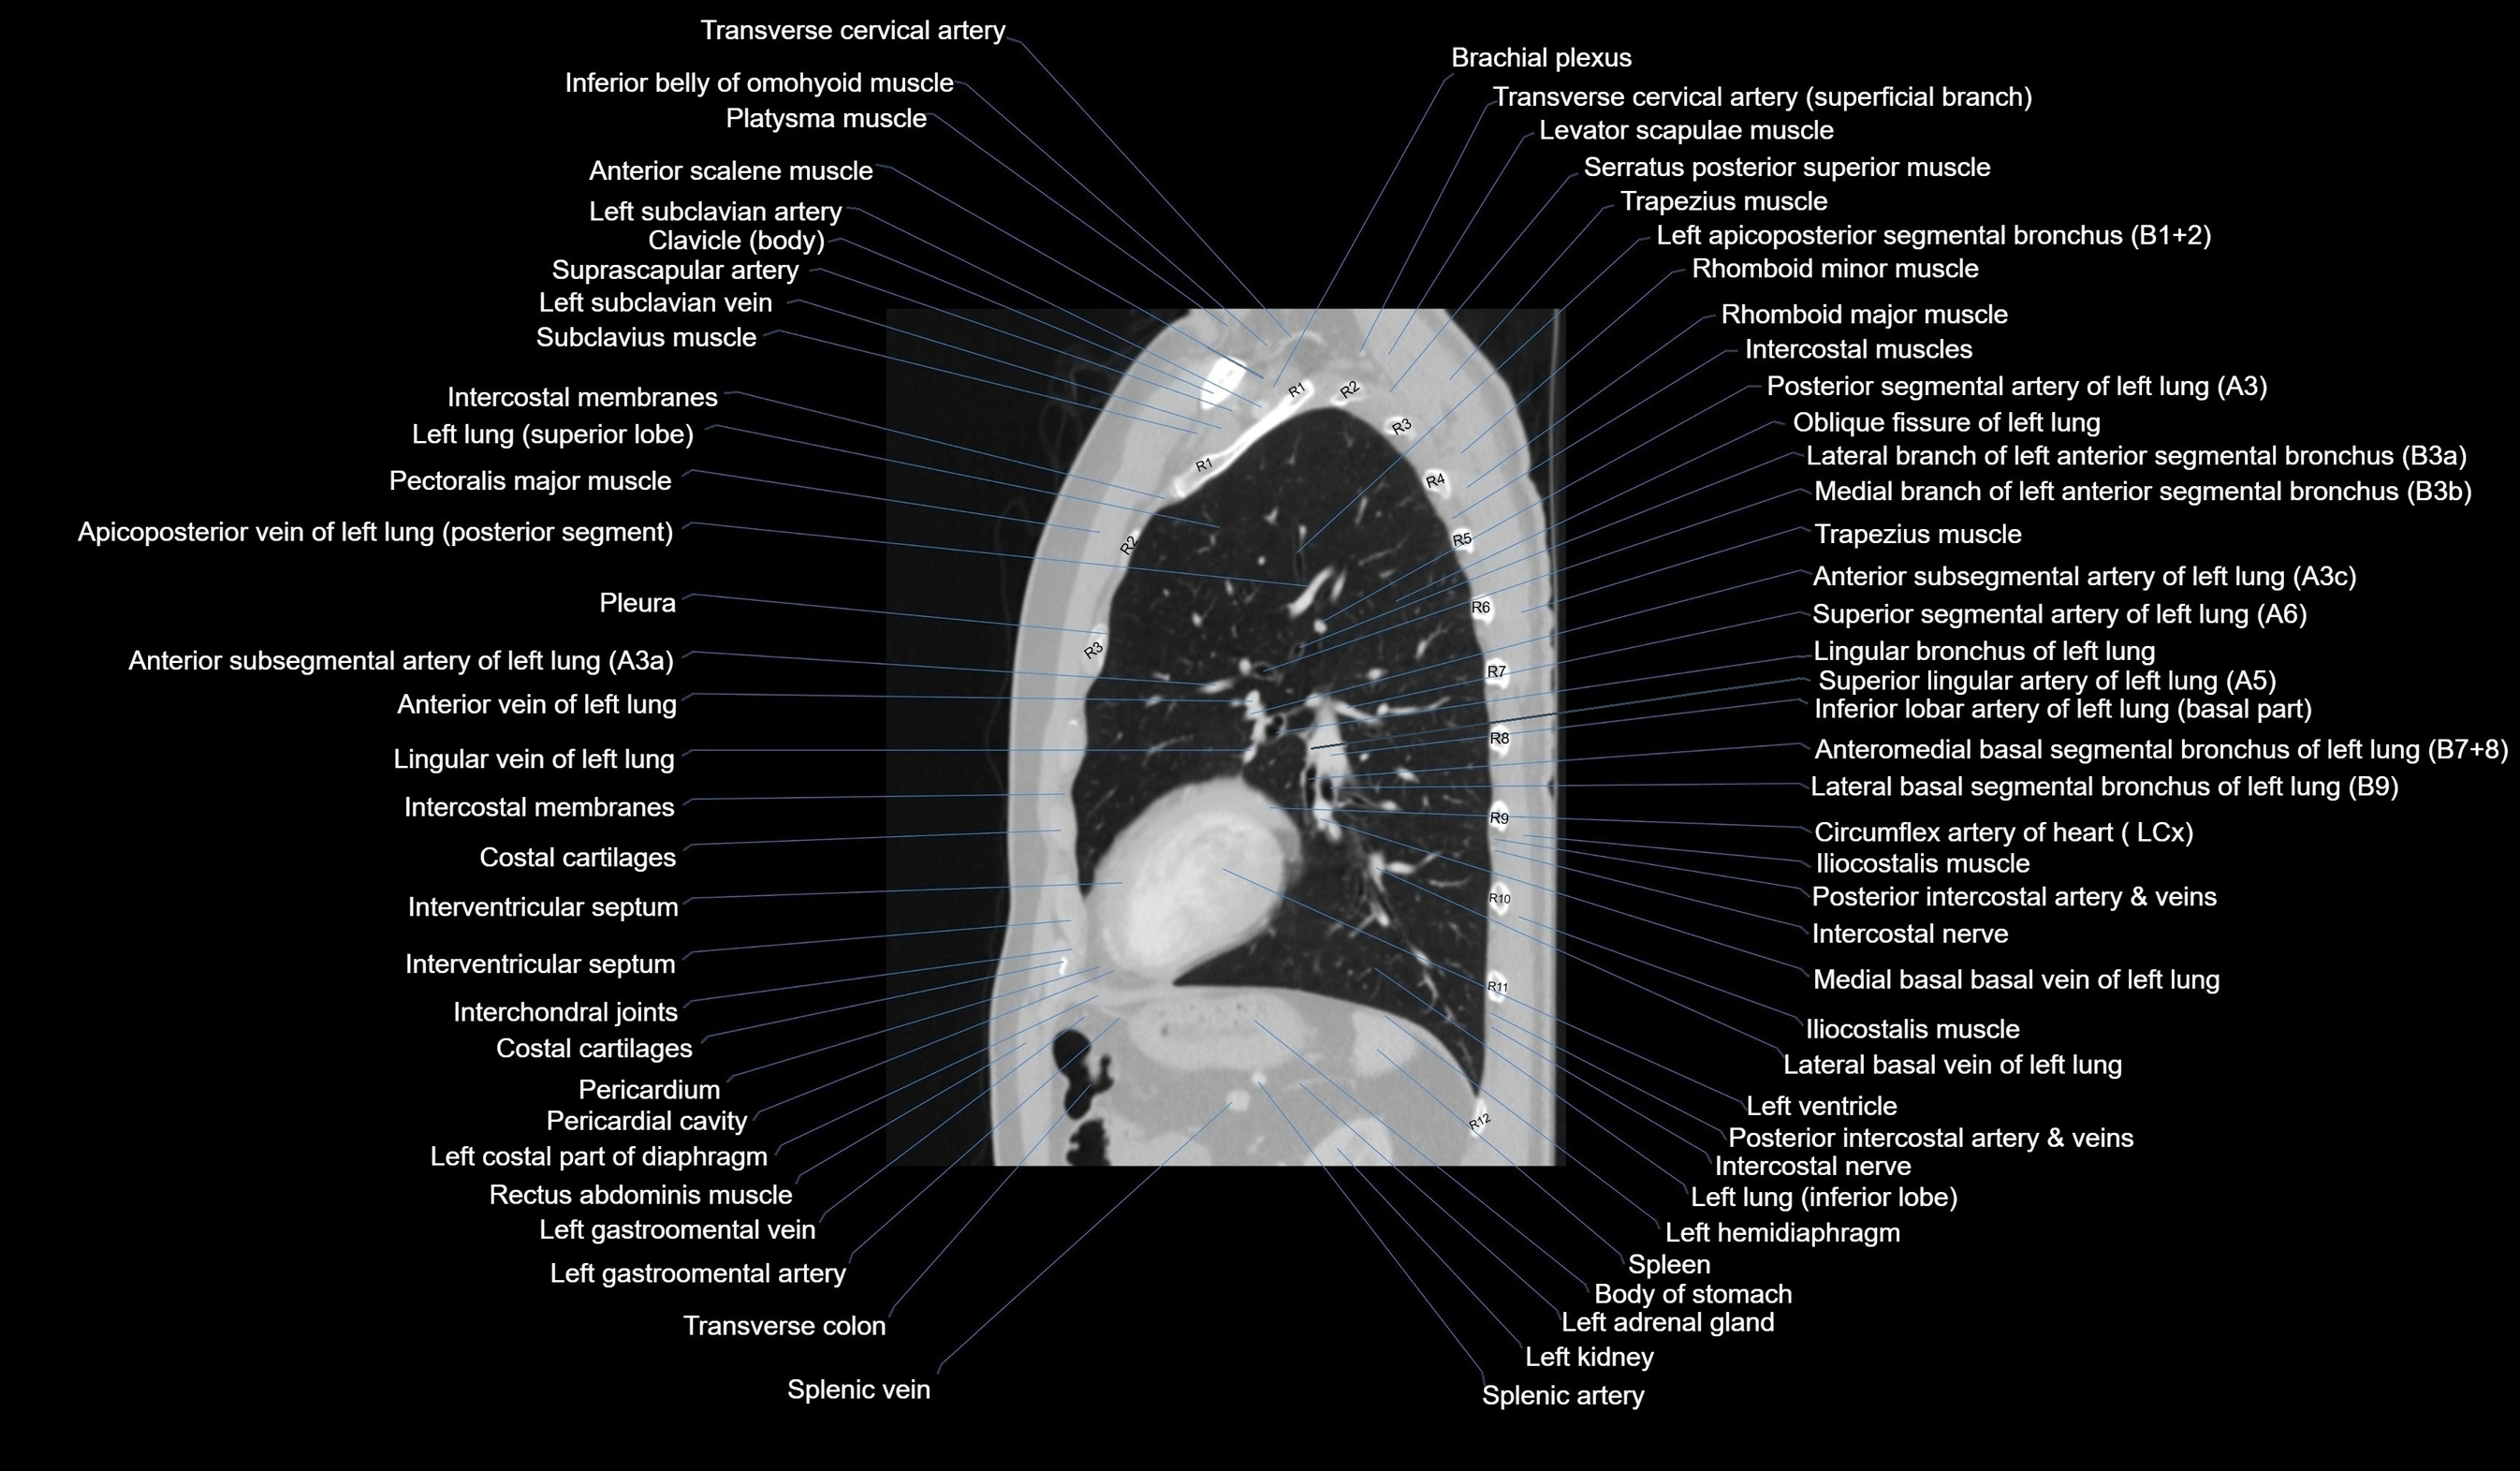

- T (Thoracic spine)